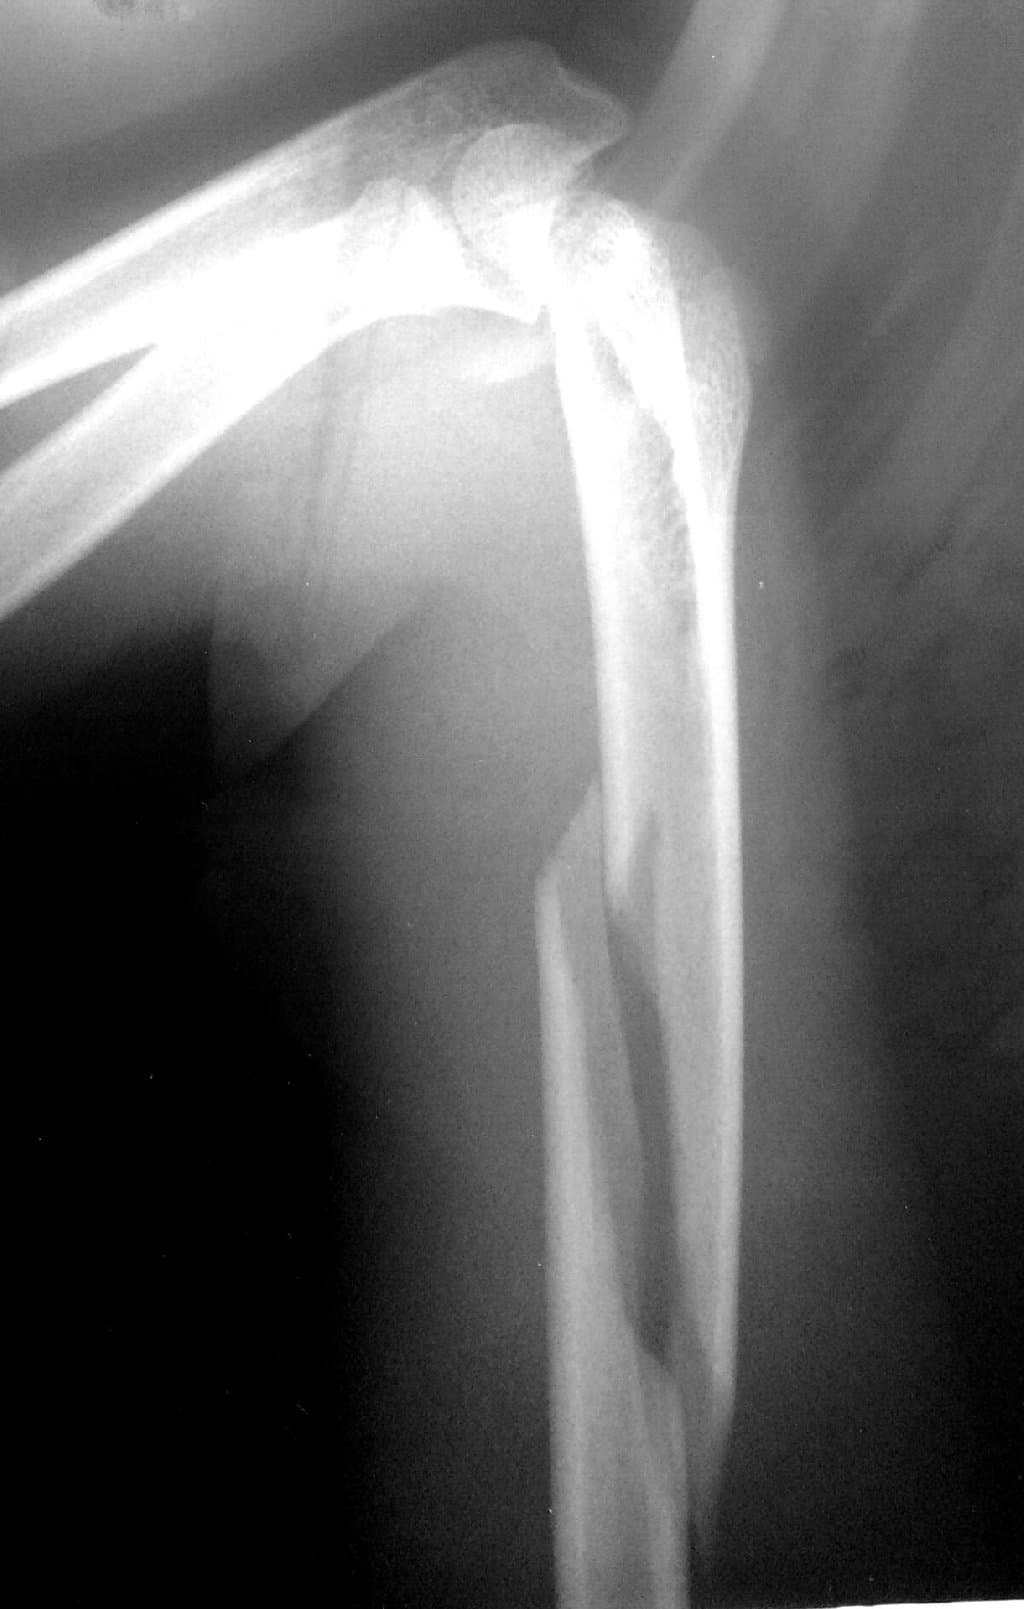

Diaqnoz

Diaqnoz üçün adətən fiziki müayinə və röntgen çəkilişləri istifadə olunur. Bəzən, daha dəqiq diaqnoz üçün CT (Kompüter Tomografiyası) və ya MRI (Maqnit Rezonans Görüntüləmə) kimi əlavə görüntüləmə testlərindən də istifadə edilə bilər.